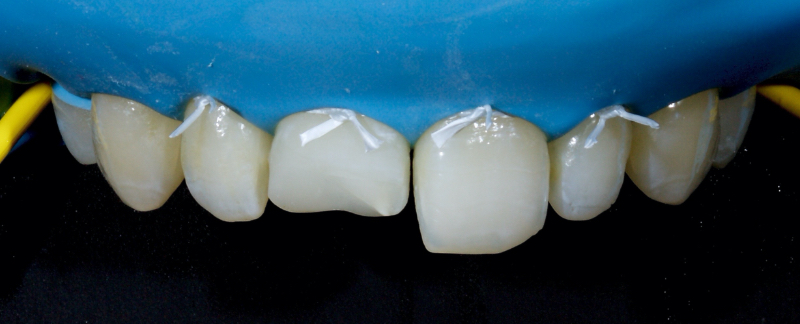

In this example of the Modified Walking Bleach Approach, the patient presented with a discolored upper right central incisor (1.1, Fig. 7). The old restoration was removed, an endodontic retreatment was carried out, and a coronal barrier seal was placed (Fig. 8). The access cavity was left open (Fig. 9).

The patient carried out the modified walking bleach technique with a nightguard for 48 hours (Fig. 10). I prefer to mark the night guard with a Sharpie marker to enable the patient to visualize the correct tooth to treat. The patient returned for review after successful whitening (Fig. 11).